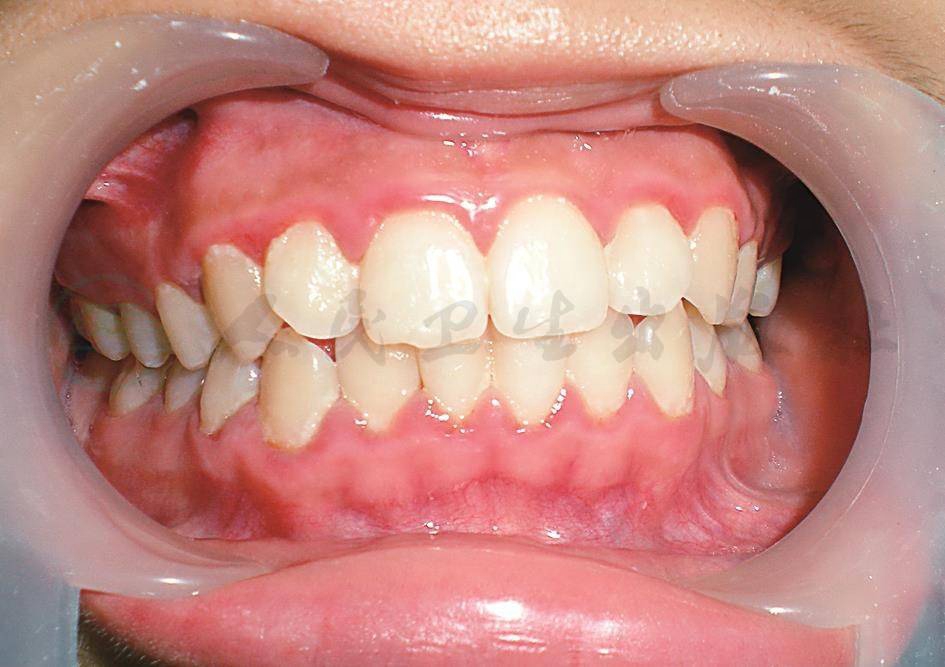

牙龈炎症一般局限于游离龈和龈乳头,以前牙区为主,表现为龈缘和龈乳头红肿(图1),易出血,龈沟液量增多,局部有牙垢和食物残渣附着,一般无自发性出血,而用钝头探针轻探龈沟即可出血,探诊出血(bleeding on probing,BOP)对龈炎的早期诊断有意义。

图1菌斑性龈炎

患儿,女,13岁,因刷牙出血前来就诊,临床检查表现为上、下颌前牙龈缘红,稍肿